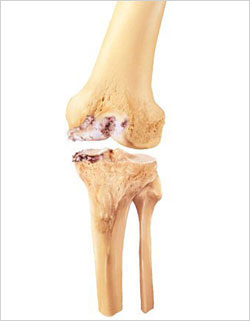

Figure: Medial compartment osteoarthritis

The knee is made up of three compartments: the medial compartment (located on the inside of the knee), the lateral compartment (located on the outside of the knee), and the patellofemoral compartment (located in the front of the knee). In a particular group of osteoarthritis patients, however, the entire knee is not affected by the arthritis. In some patients, only the medial compartment (or, less commonly, only the lateral compartment) may be affected by the disease. For those patients, unicondylar (partial) knee replacement can be considered a treatment option. The term “unicondylar” refers to the replacement of only one section of the smooth bone ends (condyles) – the medial or lateral compartment – as compared to total knee replacement, which involves replacement of all three compartments.